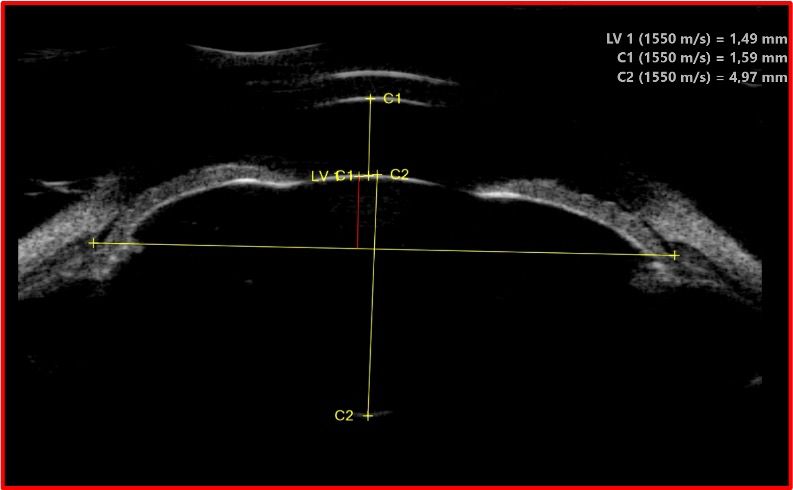

Corps ciliaire et sulcus

L'UBM est la seule technique d'imagerie permettant de visualiser le corps ciliaire dans sa totalité : processus ciliaires, pars plana, zonules. Elle mesure le sulcus ciliaire (diamètre sulcus-à-sulcus), donnée indispensable pour le dimensionnement des implants phakes ICL (Implantable Collamer Lens). Un mauvais dimensionnement peut entraîner un glaucome par contact iris-implant ou une cataracte par contact cristallin-implant.

Implants et chirurgie

L'UBM contrôle le positionnement des implants intraoculaires : implants de chambre postérieure (vaulting de l'ICL par rapport au cristallin), implants de chambre antérieure (distance par rapport à l'endothélium cornéen), implants suturés à la sclère. Elle évalue également les complications post-opératoires : déplacement d'implant, synéchies antérieures, fibrose capsulaire.

UBM du segment antérieur — Anatomie haute résolution UBM — Biomicroscopie ultrasonore du segment antérieur Anatomie du segment antérieur Chambre antérieure Cornée Épithélium + stroma + endothélium Iris Corps ciliaire + processus ciliaires Cristallin Angle Diamètre sulcus-à-sulcus (mesure ICL) 50 MHz Image UBM résultante Cornée Chambre antérieure Iris Iris Cristallin CC CC Angle 1 mm Avantages de l'UBM Visualise derrière l'iris (impossible en OCT) | Résolution 25-50 µm | Mesure du sulcus pour ICL

Biomicroscopie ultrasonore (UBM) à 50 MHz : l'anatomie du segment antérieur (à gauche) est reproduite avec une résolution exceptionnelle sur l'image UBM (à droite). L'angle irido-cornéen, le corps ciliaire (CC) et le sulcus sont visibles en détail, permettant le diagnostic du glaucome par fermeture de l'angle et le dimensionnement des implants phakes.